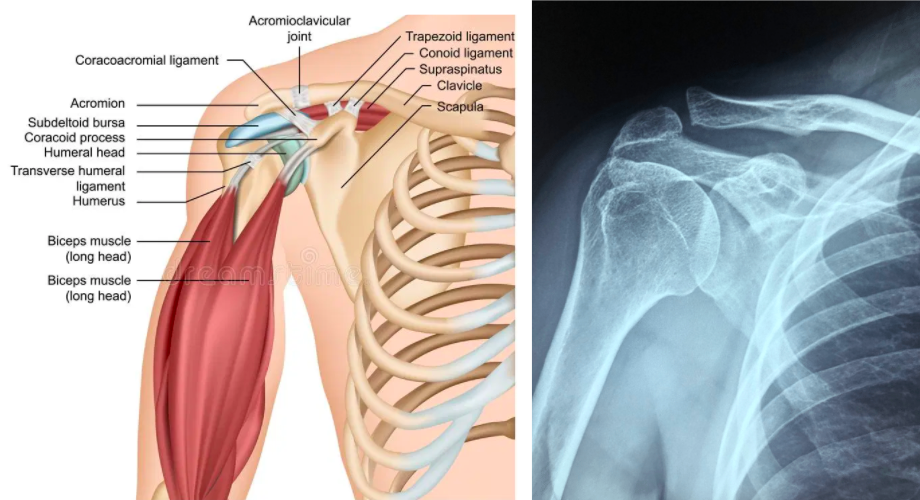

Comprendre l’articulation de l’épaule : petits rappels anatomiques

L’articulation de l’épaule est complexe et constitue l’articulation du corps la plus instable mais aussi la plus mobile. Elle se compose de plusieurs articulations permettant de bouger le bras dans presque toutes les directions avec de larges amplitudes articulaires. L’épaule est composée de 3 os : l’humérus, l’omoplate et la clavicule.

Dans le complexe de l’épaule, nous distinguons des articulations dites vraies (entre deux os) et des articulations dites « fausses » (entre un os et un muscle ; ce sont des plans de glissement). Nous retrouvons 5 articulations :

3 articulations vraies :

- L’articulation gléno-humérale qui relie l’humérus à la glène de l’omoplate. C’est l’articulation principale de l’épaule.

- L’articulation acromio-claviculaire reliant l’acromion de l’omoplate avec la partie latérale de la clavicule.

- L’articulation sterno-costo-claviculaire entre le sternum, l’avant du thorax et la partie interne de la clavicule.

2 articulations « fausses » :

- L’articulation scapulo-thoracique permet un glissement de la face antérieure de l’omoplate, recouverte de muscle, sur le grill costal postérieur.

- L’articulation sous-acromiale entre l’acromion (processus osseux de l’omoplate) et les muscles qui enveloppent la tête de l’humérus. Cette articulation se fait par l’intermédiaire d’une bourse de glissement que l’on nomme bourse sous-acromio-deltoïdienne.

C’est l’ensemble de ce complexe articulaire qui permet la mobilité du bras. Cependant, du fait de la faible congruence articulaire, l’épaule est instable. Ce sont les muscles qui entourent l’articulation qui permettent la stabilisation. Ces muscles sont au nombre de 5 et se nomment « muscles de la coiffe des rotateurs ». Parmi eux nous avons :

- Le muscle supra-épineux,

- Le muscle infra-épineux,

- Le muscle petit rond,

- Le muscle sous scapulaire,

- Le muscle long biceps.

Comme dans toutes les articulations du corps, l’épaule est aussi maintenue par des ligaments